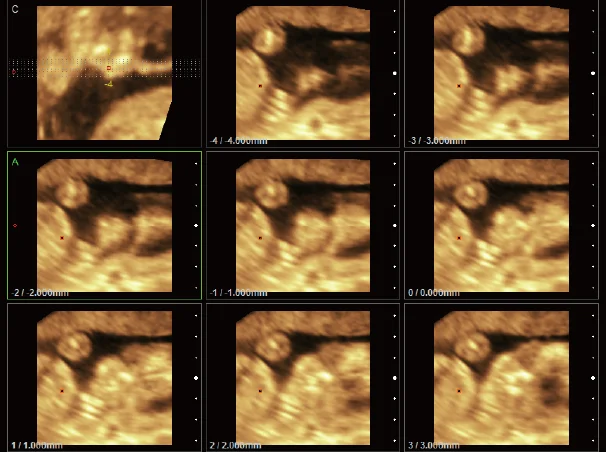

Ultrasound

Wide range of Ultrasound machines that suites a variety of applications from abdominal to rectal scans, we take in consideration how the world is moving towards mobility and mobile applications.

EBIT50/60 VET

All the power you need

The EBit provides all the power you need for today´s challenging clinical environment, yet remain ultra-portable, ultra-affordable. With its cutting-edge imaging technologies, precise and intuitive workflow, ergonomic and eco-friendly design, versatile transducers for all applications from top to toe, we firmly believe the EBit to be the very best portable ultrasound in its class today.

ECO5 VET

Ultra-Portable, Ultra- Affordable, Color doppler

The multi-purpose user presets, comprehensive measurement & report system, built-in EasyView image achieve system, quick image storage / retrieve / transfer, one-button direct print, make the complete workflow better than what you can dream of.